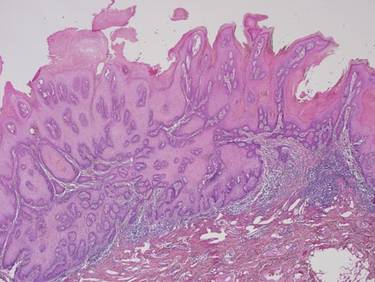

При хистопатологично изследване се установява че туморните лезии в началния стадий особено в повърхностните си части имат прилика с брадавици. Налице е хиперкератоза, паракератоза и акантоза. Кератиноцитите са еозинофилни и имат малки ядра. Хистологично по-голямата част от тумора е съставена от добре диференциран сквамозен епител. Екзофитната повърхност включва дълги папиломатози гънки, които обикновено са покрити от голямо количество орто- и паракератин. Последният покрива и дълбоката част на инвагинациите. Не съществува единно становище по въпроса дали верукозният карцином е самостоятелна нозологична единица или всъщност е екзофитна форма на спиноцелуларния карцином; в последно време обаче се приема че всъщност карциномите на покривния епител са само два типа - базоцелуларен и спиноцелуларен. Следователно верукозният карцином се класифицира към плоскоклетъчния карцином. В подкрепа на това становище е наличието на много смесени варианти - верукозен карцином, сред клетките на който се откриват гнезда от клетки на типичен плоскоклетъчен карцином - коекзистенция на два малигнени тумора. Много често се наблюдава и анапластична трансформация - първоначално се развива типичен верукозен карцином, който впоследствие се превръща в типичен плоскоклетъчен карцином. При наличие на гнезда на спиноцелуларен карцином биологичното поведение на тумора е потенциално по-малигнено в сравнение с вариантите без такива гнезда. Подтип на верукозния карцином е Epithelioma cuniculatum (Carcinoma cuniculatum или тумор на Ackerman по името на откривателя). Този тумор съдържа добре диференцирани епителни клетки с нисък клетъчен атипизъм. Има грапава повърхност и дълбоки инвагинации, изпълнени с кератин. Те навлизат на голяма дълбочина в съединителнотъканната строма, която е нежна и не съответства като количество на обилно разрастващия туморен паренхим.

Верукозен карцином - в много участъци образуванието наистина прилича на брадавица. Въпросът дали брадавиците са преканцероза и дали на базата им възникват малигнени тумори е все още дискутабилен. Все пак макроскопски и особено микроскопски верукозният карцином много наподобява брадавиците, както се вижда на хистологичните срезове. От там произлиза и названието на този тумор, който определено се класифицира към малигнените неоплазми. В миналото изследователите са оприличили верукозния карцином на verruca vulgaris и затова са го нарекли именно по този начин. Това обаче не бива да отключва канцерофобии у нито един пациент, тъй като брадавици има почти всеки индивид на планетата Земя и далеч не всяка от тях дегенерира в карцином - дори развитието на верукозен карцином на тази база е по-скоро казуистична рядкост. Хигиената, редовните профилактични прегледи дори само при общопрактикуващ лекар, избягването на алкохола и тютюнопушенето са достатъчни за превенцията на развитието на малигнени процеси в човешкия организъм.